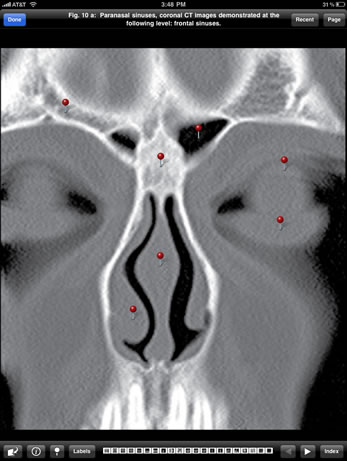

Preview the Imaging Atlas of Human Anatomy, featuring select images of the healthy human body as seen through a wide range of modern imaging techniques.

This Sampler is based on the print atlas, the Imaging Atlas of Human Anatomy, 4th Edition, written by Jamie Weir, Peter Abrahams, Jonathan D. Spratt, and Lonie Salkowski. The complete Atlas, also available in the modalityBODY Store, offers a comprehensive view of the structures and relationships within the body through a variety of imaging modalities.